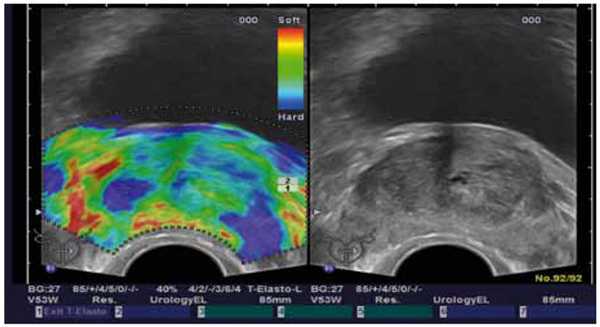

Американские исследователи подчеркивают приоритетное значение этой технологии в ультразвуковой диагностике РПЖ. Метод основан на определении не только ультразвуковых характеристик, но и эластичности ткани предстательной железы (рисунок 4).

Рисунок 4. Эластография: мультифокальный РПЖ

Известно, что злокачественные клетки расположены очень плотно, а эластичность опухоли резко снижена. Это и определяет уролог при пальцевом исследовании предстательной железы. Однако, каменистая плотность свидетельствует, как правило, о распространенном процессе. На ранних стадиях - пальпаторно определить уплотнение в железе невозможно. Ультразвуковой аппарат с функцией эластографии, помимо получения изображений в режиме серой шкалы, позволяет осуществлять цветовое картирование зон с различной эластичностью: обычная ткань окрашивается зеленым цветом, а ткань, подозрительная на неопроцесс - синим. При использовании эндоскопического датчика можно определить инвазию опухоли в капсулу предстательной железы.